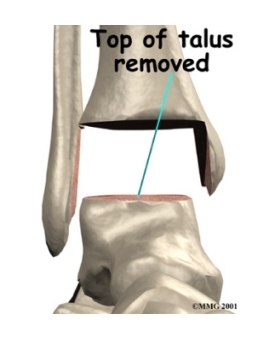

- The talus component replaces the top of the talus.

The tibial component is usually made up of two parts: a flat metal piece called a metal tray that is attached directly to the tibia bone, and a plastic cup that fits onto the metal piece, forming a socket for the artificial ankle joint. The talus component is made of metal and fits into the socket of the tibial component.